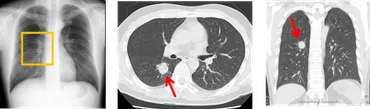

肺がんの早期発見には、低線量CT検査が有効です。

この検査は、被ばく線量を抑えながら、小さな病変も検出できるため、早期発見に繋がります。

✅ 肺がんは日本人の死亡原因の第一位であり、早期発見のためには、胸部X線検査よりも小さな病変を検出できる低線量胸部CT検査が有効です。

早期発見のためには、定期的な検査が重要であり、リスクの高い人は低線量胸部CT検査(LDCT)などの検査を受けることが推奨されます。